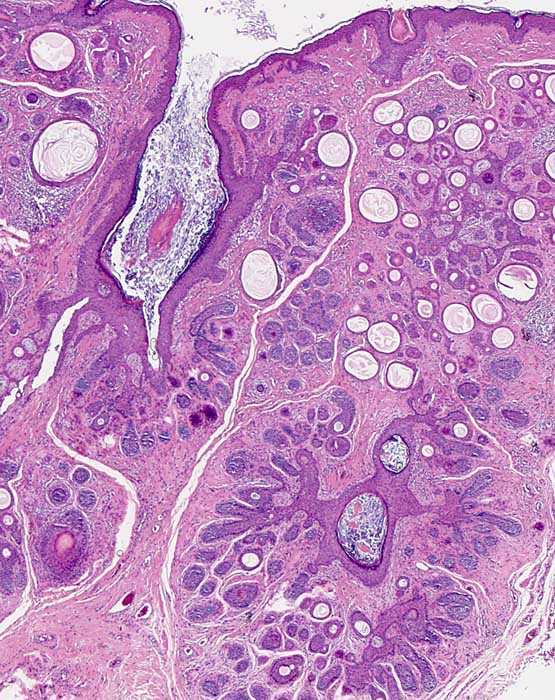

Trichofollikulom

benigner Tumor

Haut, Kopf

Haut

Zwei dilatierte Haarfollikel werden von kleineren Follikeln strahlenförmig umlagert. Die dilatierten Follikel sind gefüllt mit Hornmaterial. Aus den kleineren Follikeln sprossen wiederum weitere Follikel aus.

Kleine Papel am Kopf.

Histologie

25